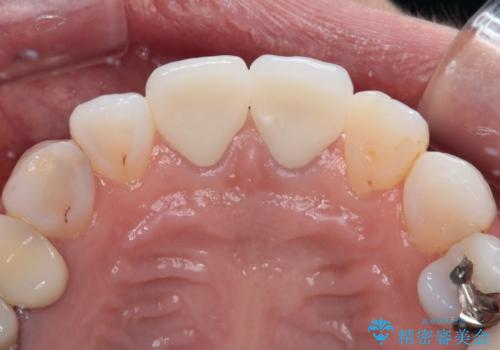

- 変色した保険の前歯のクラウンを交換したいとのことで来院された患者様です。

中心左側の歯はクラウンが装着されており、右側は神経組織が除去されて多少変色している状態でした。

右側の歯も将来的にもっと変色する可能性があるため、前歯2本をオールセラミッククラウンにて補綴治療を行うこととしました。